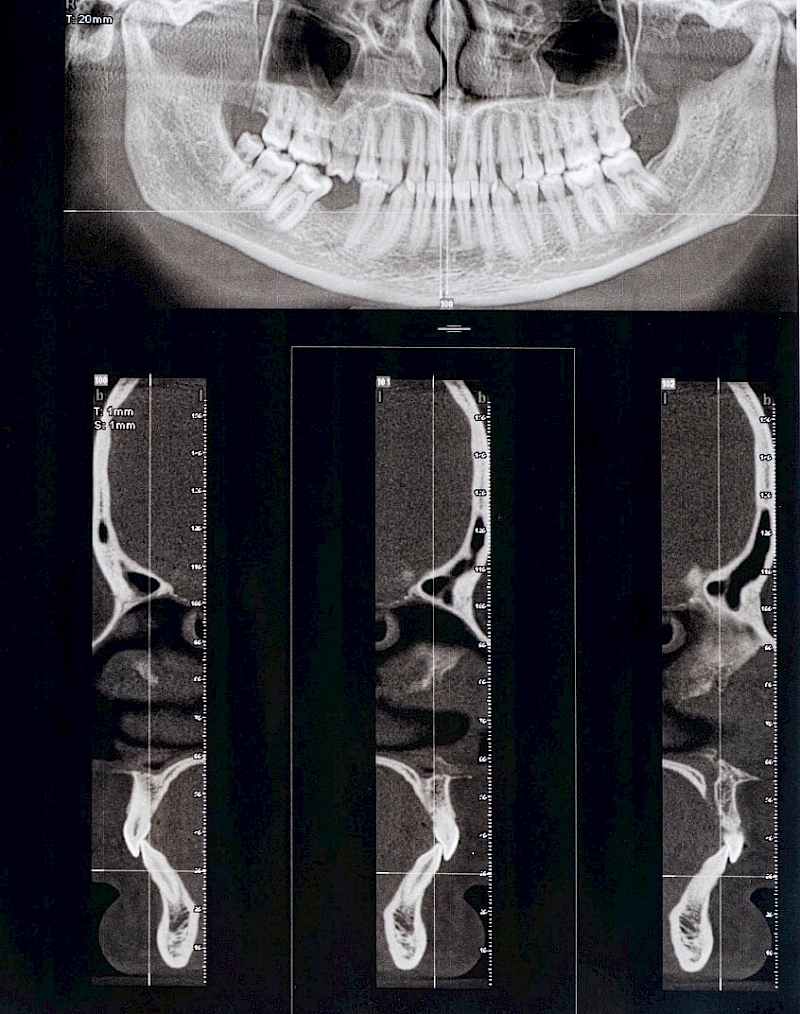

Displacement of the disc or degenerative changes in the condyle and disc may also occur in the TMJ. Differences in clinical symptoms in the TMJ cannot always be explained as disc displacement. The function and dysfunction of the masticatory muscles should also be taken into account.

Degenerative joint disorders, osteoarthritis, arthrosis,